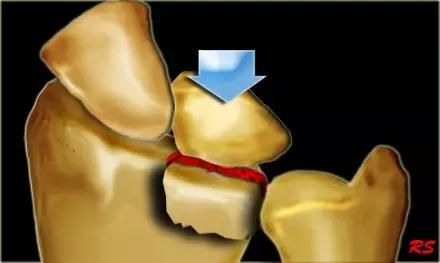

5. Hoffa 骨折

指股骨远端冠状面的骨折。

病例 1:一般股骨髁间、髁上粉碎骨折中含 Hoffa 骨折的不少见,但单纯后髁骨折则很少见。